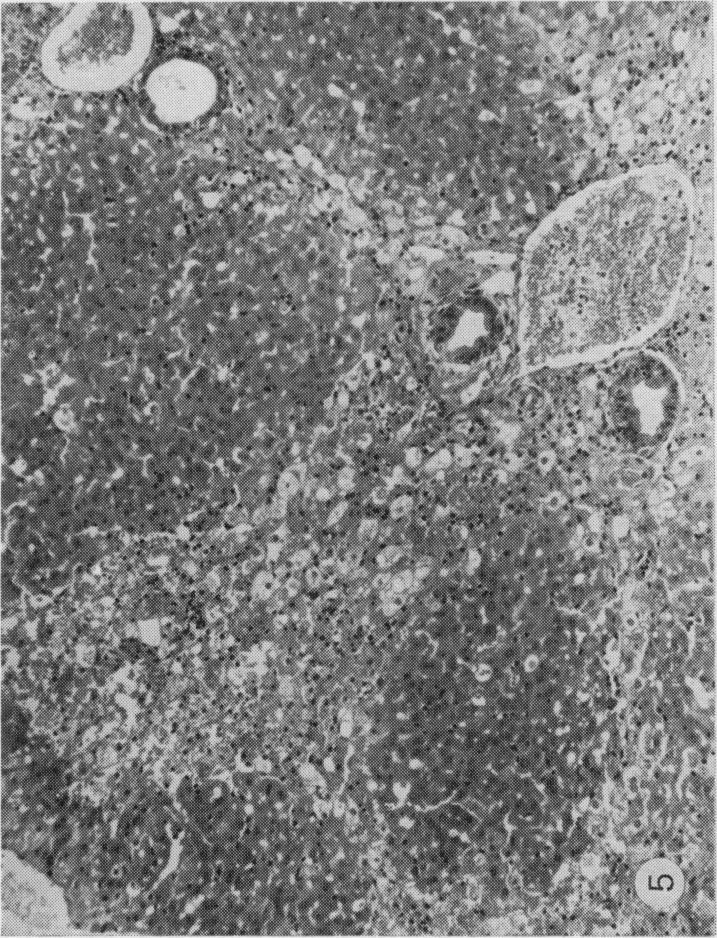

Male Syrian hamsters, 8-10 weeks of age, were treated with a single intraperitoneal injection of crystalline aflatoxin B1 in solution of N -N -Dimethylformamide (DMF). The concentrations of aflatoxin were adjusted to the smallest controllable amount of solvent in relation to the size of the animal (0-5 or 1-0 ml/kg). Treatment with, respectively, 5-0 or 2-5 mg/kg aflatoxin in 1-0 ml/kg DMF was lethal to most animals within one week. However, reduction of the solvent to 0-5 ml/kg, while not eliminating the mortality entirely during the first week, made possible observation of the survivors up to 28 days. Hamsters appear to be more susceptible to DMF poisoning than other species, like rat, guinea-pig and rabbit in which this solvent was used by investigators on the biological effects of aflatoxin. Either dose given of DMF alone was lethal for several animals during the first week of observation and sufficient to produce histological lesions in the liver which were characteristic and clearly different from those induced by aflatoxin during the same period. DMF alone caused centrilobular necrosis which was accompanied by haemosiderosis of liver structures. With a aflatoxin, in addition, periportal and midzonal necrosis of the liver was present. Aflatoxin B1 and B1 and DMF both induce haemorrhagic tendency probably involvement in the coagulation process of the blood. It cannot be decided, however, at present whether this is the result of an indentical mechanism.

8至10周龄的雄性叙利亚仓鼠经腹腔注射一次溶解于N -N -二甲基甲酰胺(DMF)中的结晶黄曲霉毒素B1进行处理。根据动物体型将黄曲霉毒素的浓度调整至溶剂的最小可控量(0 - 5或1 - 0毫升/千克)。分别用1 - 0毫升/千克DMF中5 - 0或2 - 5毫克/千克的黄曲霉毒素处理,在一周内对大多数动物是致命的。然而,将溶剂减少至0 - 5毫升/千克,虽然不能完全消除第一周的死亡率,但使得观察存活者长达28天成为可能。仓鼠似乎比其他物种,如大鼠、豚鼠和兔子,对DMF中毒更敏感,研究人员曾用这种溶剂研究黄曲霉毒素的生物学效应。单独给予任何一种剂量的DMF在观察的第一周内对几只动物都是致命的,并且足以在肝脏中产生组织学病变,这些病变具有特征性且与同期黄曲霉毒素诱导的病变明显不同。单独的DMF导致小叶中心坏死,并伴有肝脏结构的含铁血黄素沉着。此外,黄曲霉毒素还会导致肝脏的门周和中区坏死。黄曲霉毒素B1以及黄曲霉毒素B1和DMF都可能导致出血倾向,这可能涉及血液凝固过程。然而,目前尚无法确定这是否是相同机制的结果。